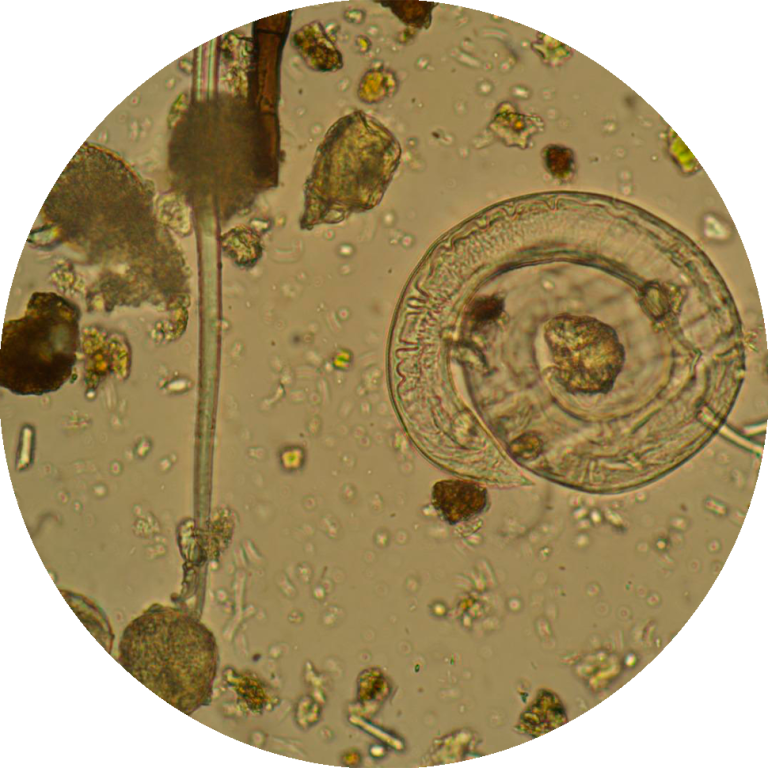

Aprofundar a Identificação Microscópica: Fornecer conhecimentos detalhados sobre a morfologia e ciclos de vida dos principais parasitas encontrados em amostras sanguíneas (ex: Babesia, Anaplasma, Dirofilaria) e fecais (ex: ovos e oocistos de nematóides, cestóides, trematóides e protozoários), utilizando as modalidades de campo claro e campo escuro.

Diferenciar Artefactos de Parasitas: Desenvolver a capacidade crítica de distinguir estruturas parasitárias reais de artefactos e contaminantes, evitando diagnósticos erróneos.

A microscopia continua a ser a técnica laboratorial de eleição para o diagnóstico de infeções parasitárias, sendo as técnicas de coloração, usadas na preparação da amostra, o fator decisivo para um diagnóstico correto e eficaz.